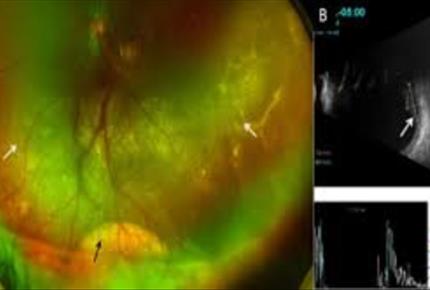

گلوکوم ثانویه به تریامسینولون-مجله مادر گوپی

گلوکوم ناشی از استروییدماهیت عینی تشخیصی است و در سالیان اخیر با افزایش مصرف استوناید تریام سینولون داخل ویتره (IVTA) برای بیماریهای مختلف ویتره و شکبیه نظیر بیماریهای عفونی، بیماریهای عروقی و بیماریهای...